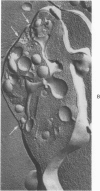

Recent reports have suggested that channels of the surface-connected or open canalicular system (OCS) in discoid blood platelets represent a reservoir of membrane that can be evaginated following activation and shape change and contribute to an increased ratio of surface area to volume. The present study has used electron cytochemistry and freeze-fracture to examine the organization of the OCS in unaltered platelets. Results of the investigation indicate that channels of the OCS are seldom if ever single tubular invaginations of the surface membrane. Each channel joins with other canaliculi of the OCS to form an anastomosing network of fenestrated conduits spreading throughout the cytoplasm from one side of the platelet to the other. The multiple connections of the interlocked channels to different sites on the platelet surface, their association in a continuous labyrinth, and participation with elements of the dense tubular system to form membrane complexes suggest that the OCS would have to be torn apart or undergo radical rearrangement before it could be evaginated and contribute to an increased surface area on activated cells.